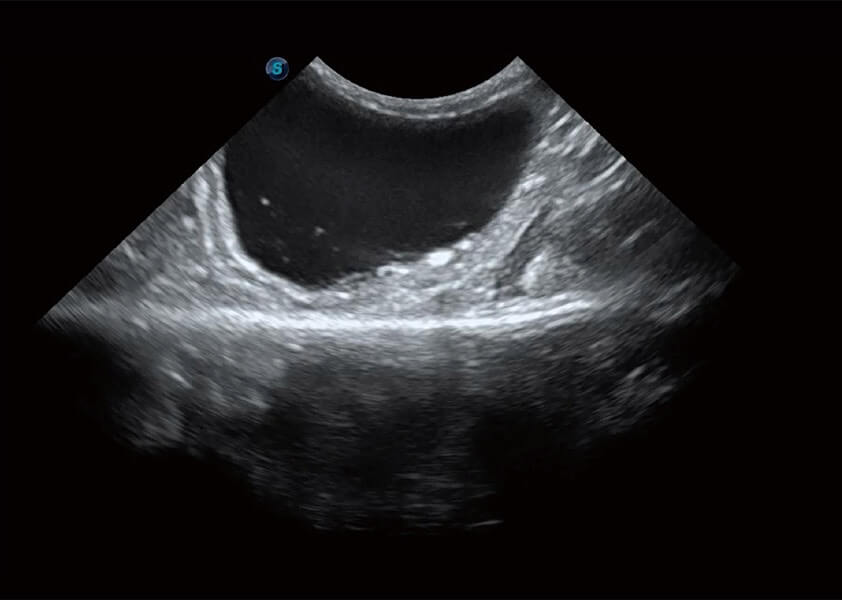

ProPet 60 作为一款高端台式动物超声设备,为动物医生的日常诊断提供了一系列贴合动物临床需求、解决临床实际问题的高级成像功能。凭借全系列高清探头,满足医生对腹部、心脏、生殖、浅表、肌骨等成像的所有需求,切实帮助您提升检查效率,提高诊断信心。

动物是人类最亲密的朋友和最值得信赖的伙伴。哈哈体育官网也一直致力于探索动物专用的超声影像解决方案。 全新推出的ProPet系列,是哈哈体育官网在动物超声影像智能化、专业化、精准化的一次跨越式革新。动物不能用言语来表述自己的不适,通过超声影像,ProPet系列搭建了动物医生与不同物种沟通的“桥梁”,为动物医生注入了“治愈之力”。